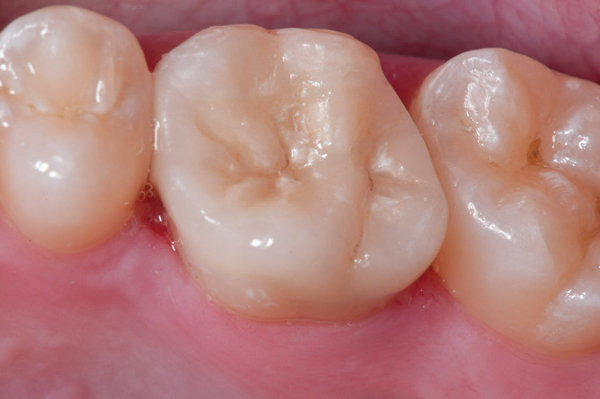

Fig 9. Preoperative view (Fig 9), preparation with composite block-out restoration (Fig 10), and final cementation of CL-IIb material (Fig 11) (final ceramic contour and stain by Steve Lee, CDT, MDC).

Fig 10. Preoperative view (Fig 9), preparation with composite block-out restoration (Fig 10), and final cementation of CL-IIb material (Fig 11) (final ceramic contour and stain by Steve Lee, CDT, MDC).

Figure 10

Fig 11. Preoperative view (Fig 9), preparation with composite block-out restoration (Fig 10), and final cementation of CL-IIb material (Fig 11) (final ceramic contour and stain by Steve Lee, CDT, MDC).

Figure 11